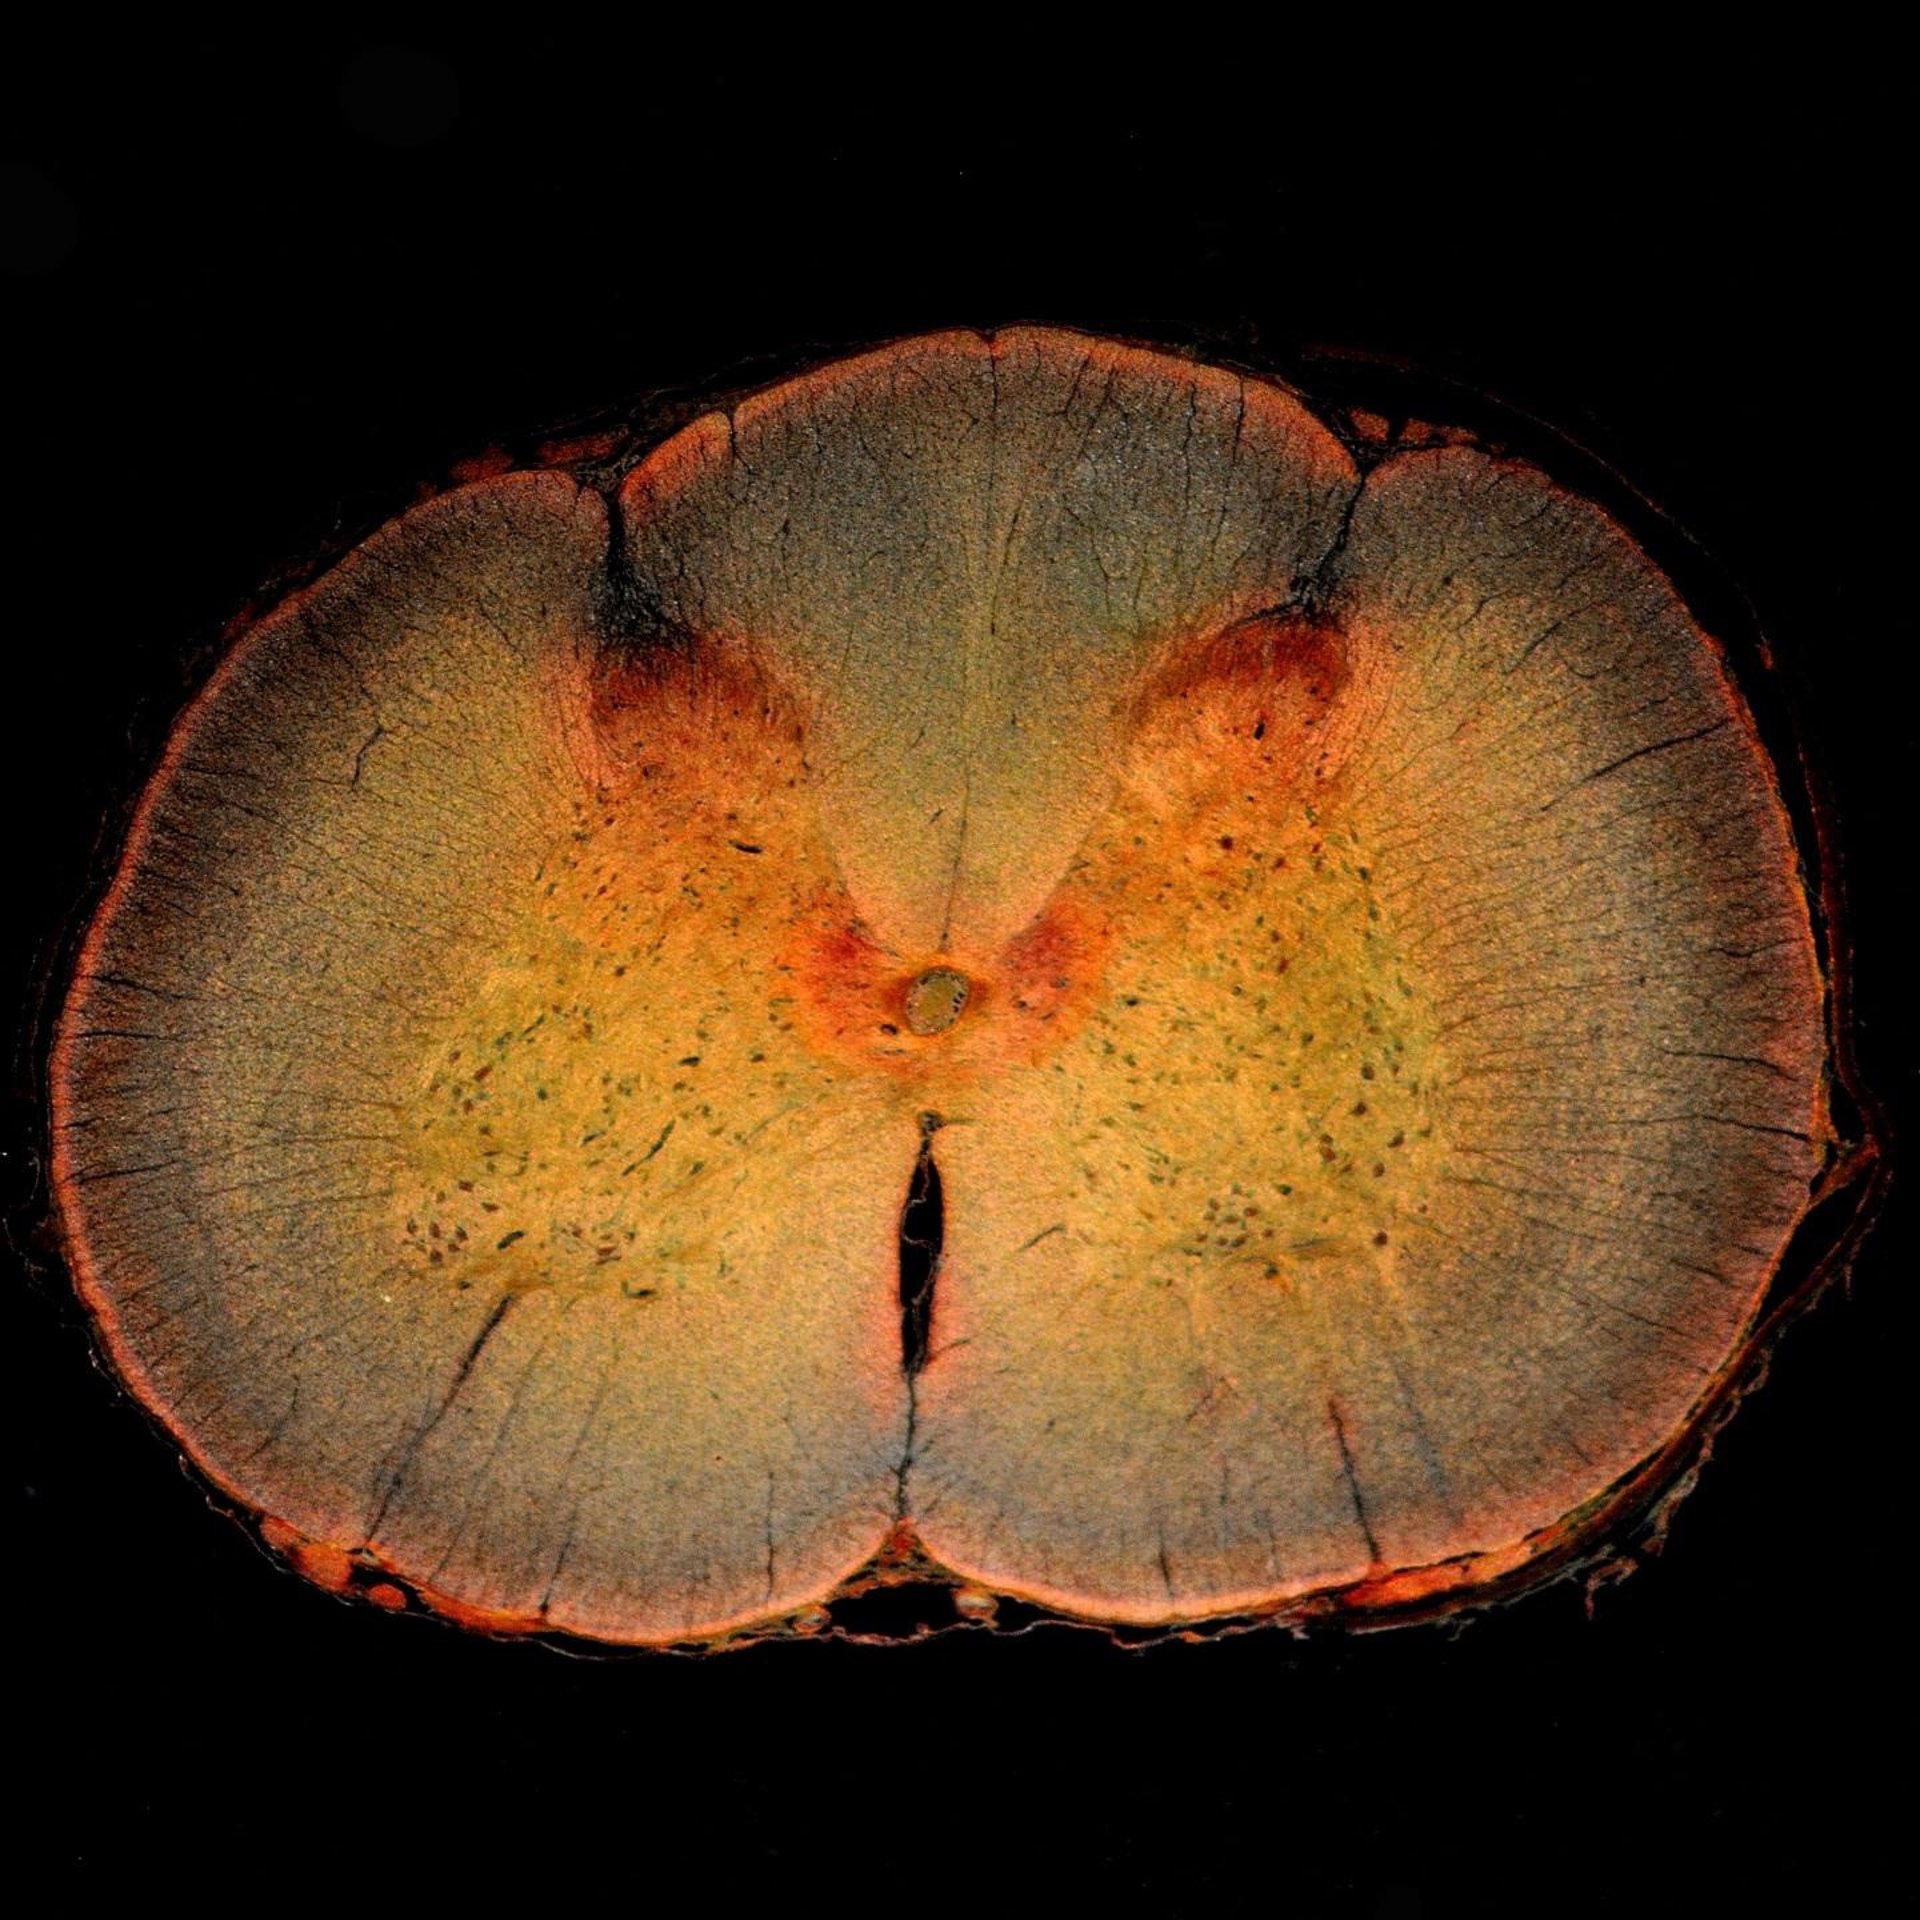

Rediseñan una enzima que podría ayudar a revertir el daño causado por una lesión - DW_ROSS / FLICKR - Archivo

Un equipo de investigadores de la Universidad de Ingeniería de Toronto (Canadá) y la Universidad de Michigan (Estados Unidos) ha rediseñado y mejorado una enzima natural que se muestra prometedora en la promoción de la regeneración del tejido nervioso después de una lesión en la médula espinal.

"Uno de los mayores desafíos para la curación después de este tipo de lesión nerviosa es la formación de una cicatriz glial", detalla la líder del estudio, Molly Shoichet. Una cicatriz glial está formada por células y bioquímicos que se unen fuertemente alrededor del nervio dañado. A corto plazo, este entorno protector protege a las células nerviosas de una lesión mayor, pero a largo plazo puede inhibir la reparación del nervio.

Hace unas dos décadas, los científicos descubrieron que una enzima natural conocida como condroitinasa ABC, producida por una bacteria llamada 'Proteus vulgaris', puede degradar selectivamente algunas de las biomoléculas que componen la cicatriz glial.

Al cambiar el entorno alrededor del nervio dañado, se ha demostrado que la condroitinasa ABC promueve el recrecimiento de las células nerviosas. En modelos animales, puede incluso llevar a recuperar alguna función perdida. Pero el progreso se ha visto limitado por el hecho de que la condroitinasa ABC no es muy estable en los lugares donde los investigadores quieren utilizarla.